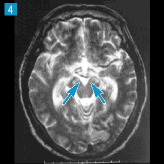

▲87ページ 経時的変化 4番目の画像内(2007/2/5)

※矢印の位置,数が誤っておりました(下は修正済みの画像です)

| ● |

|